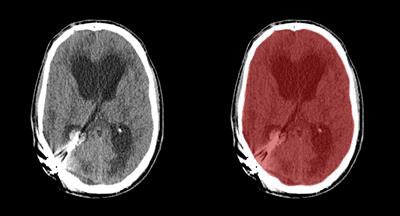

In their study, Dutch researchers developed a way to use software to automatically segment the cranial cavity based on anatomy borrowed from multiple image atlases, then refined the segmentation based on the patient's head CT data. The results closely correlated with manual segmentation of the cranial cavity in CT studies, validating the approach in a database of almost 600 patients.

Prior images in the atlas are registered to the patient image using a two-staged approach, Patel said. The first is an affine registration for a coarse alignment of the images, followed by a second, nonlinear registration to deform the atlas labels to fit the patient image. The method described is used to obtain a segmentation of the entire cranial cavity and does not differentiate between healthy or ischemic regions within the brain parenchyma. The segmentation serves as an initial step in the development of algorithms to detect and quantify anatomical regions and pathology within the cavity.

The automated results were compared with the manual annotations of trained observers, which were used as a reference standard.

The multiatlas registration results showed a high degree of overlap with the reference standard, yielding a mean Dice similarity coefficient of 0.973 ± 0.035, and adding levelset refinement increased the value to 0.984 ± 0.026.

The results encompass a large spectrum of anatomical and pathological variations seen in everyday clinical practice, and they closely approach the high performance of expert manual annotation, the authors wrote.